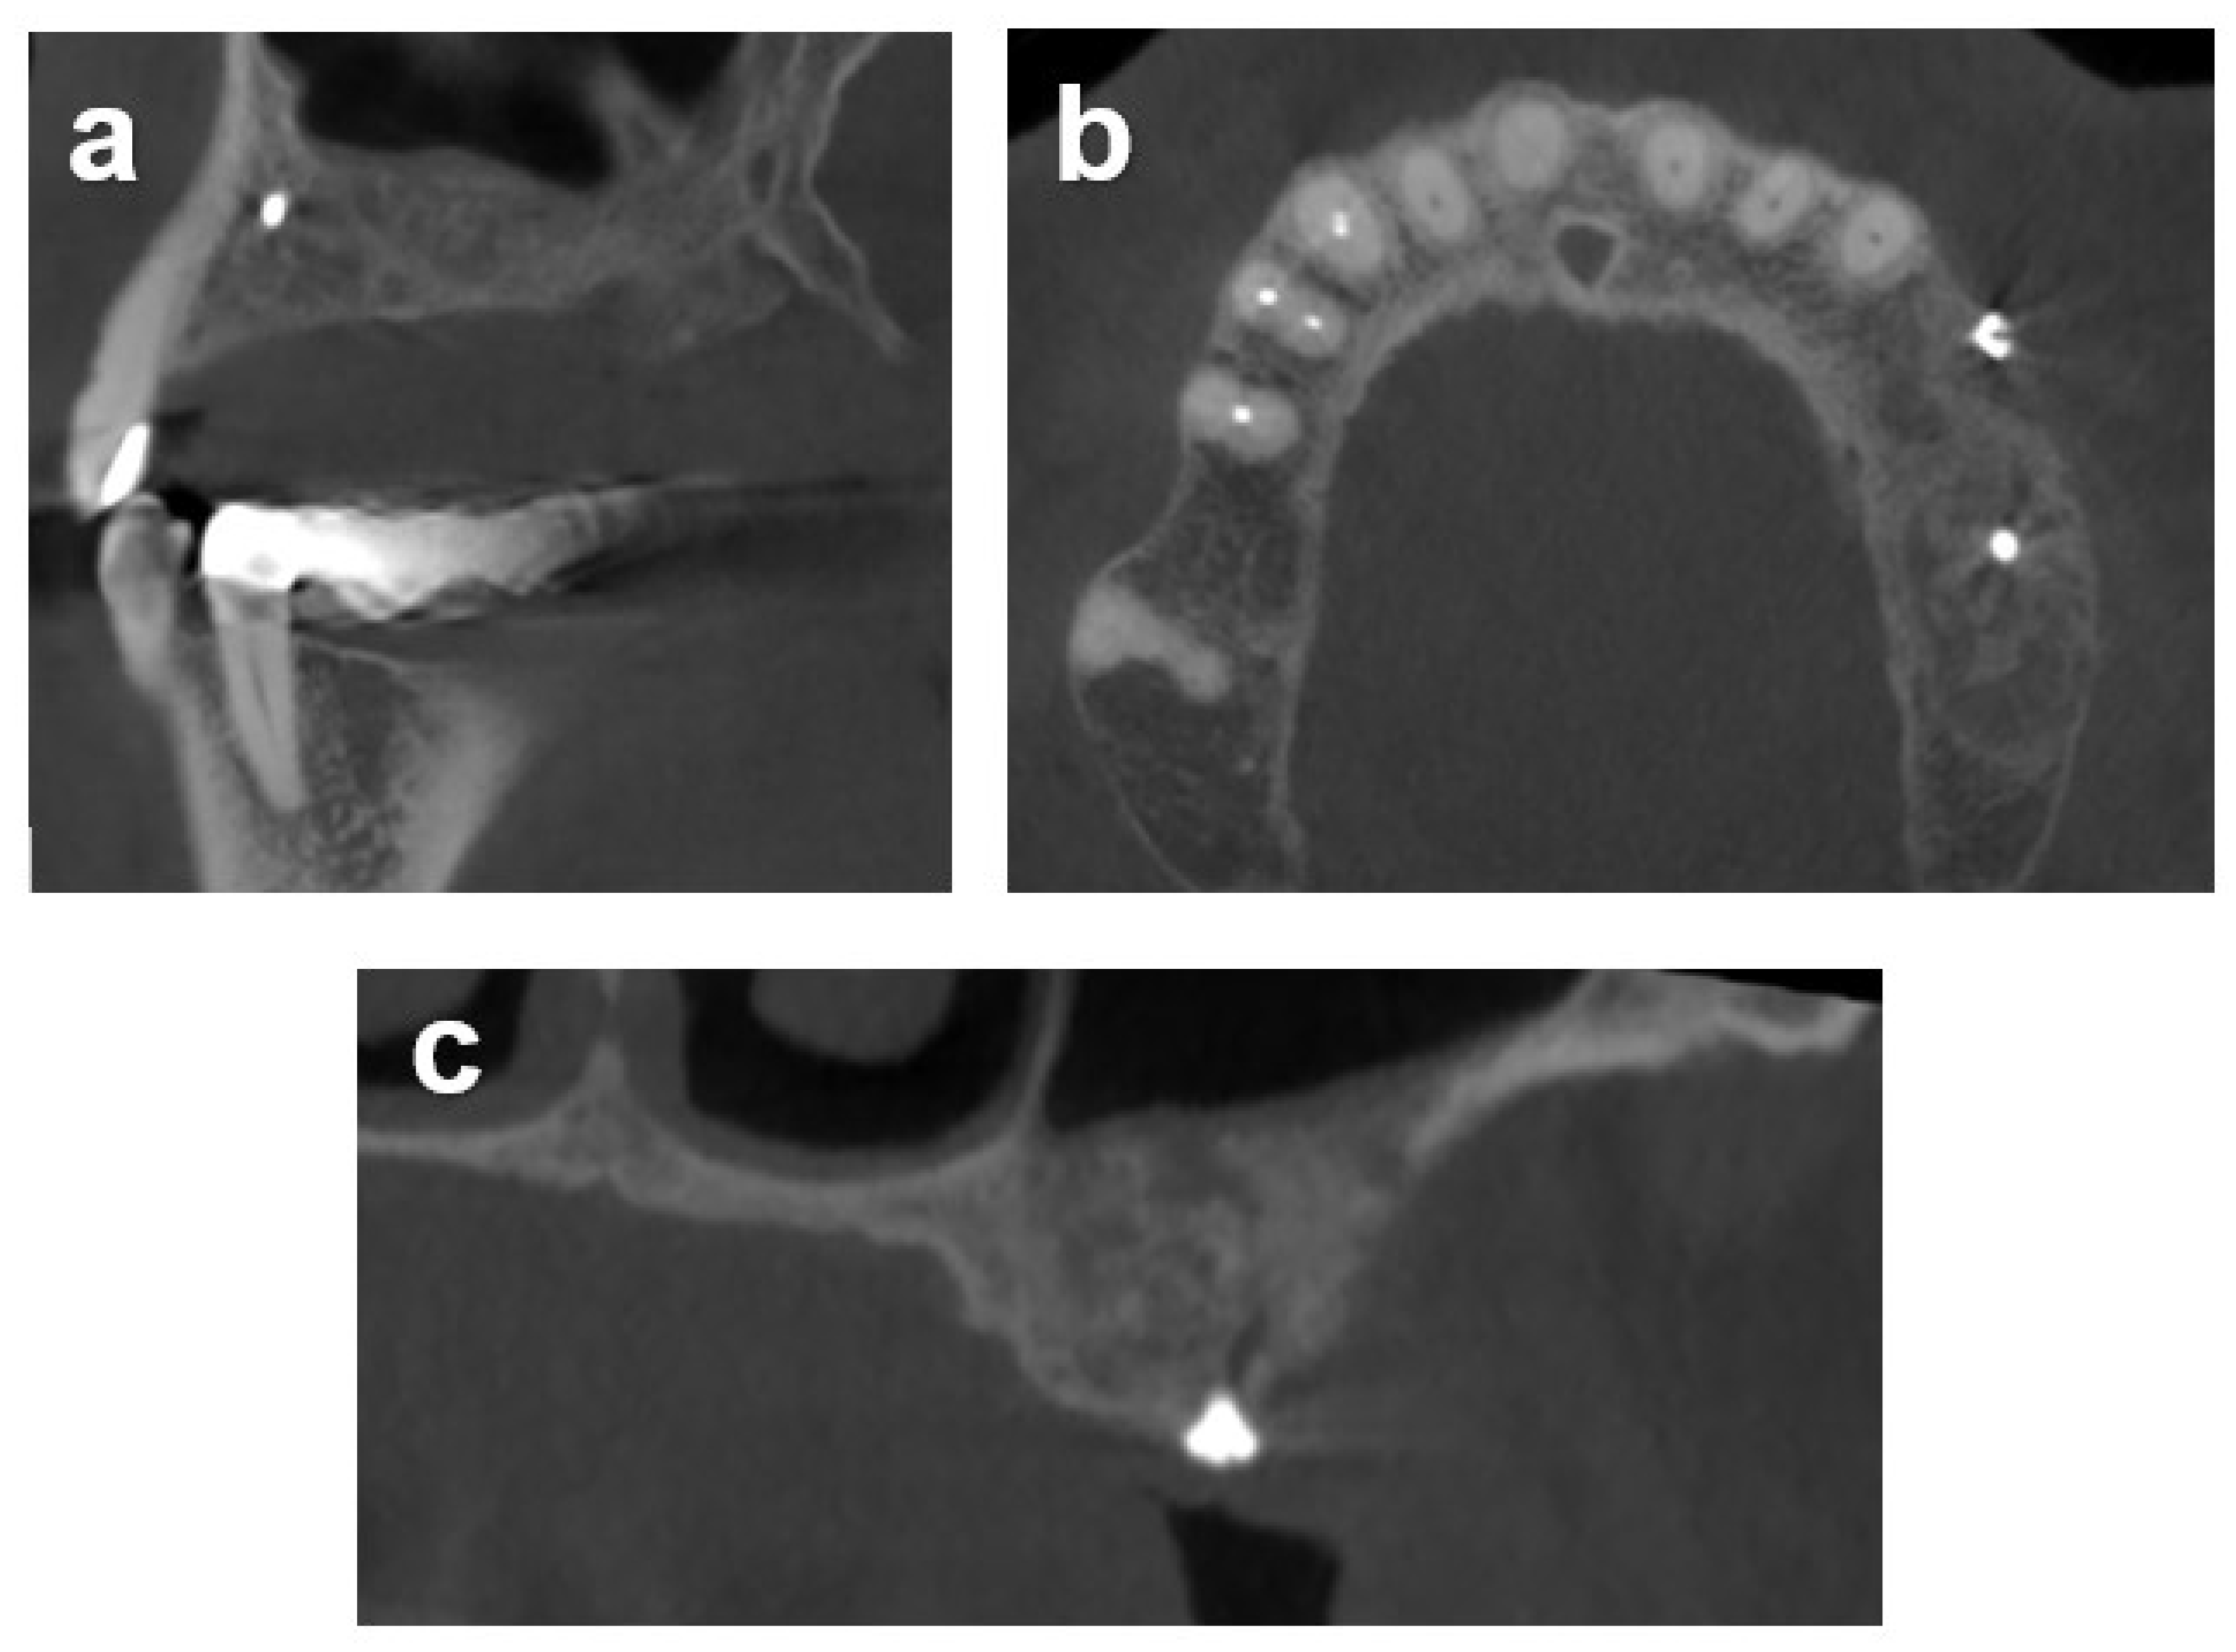

2.7.1. Case 1

2.7.2. Case 2

2.7.3. Case 3